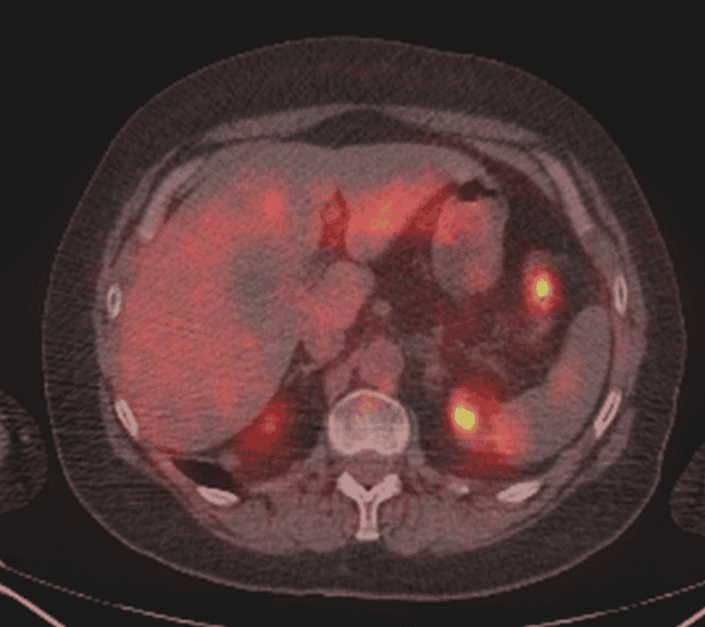

- Staging of patients with synchronous metastases at presentation that are suitable for resection or patients with equivocal findings on other imaging; for example, pulmonary or liver lesions

- Restaging of patients with recurrence being considered for radical treatment and/or invasive targeted techniques (for example, metastasectomy/selective internal radiation therapy [SIRT])

- Detection of recurrence in patients with rising tumour markers and/or clinical suspicion of recurrence with normal or equivocal findings on other imaging